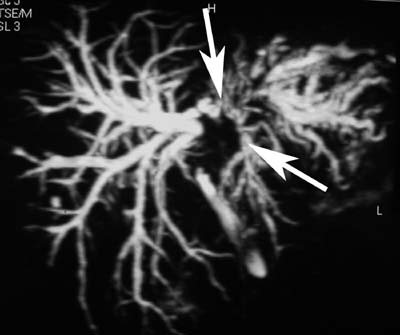

Холангиоцеллюлярный рак печени.

Рис. 2. Классификация холангиоцеллюлярного рака печени по Bismuth. Тип IV - опухоль поражает сегментарные протоки обеих долей.